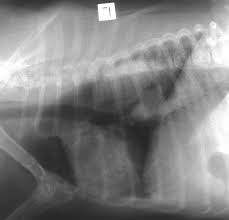

Thoracic Tumors Lung Dr Julius Liptak from images.squarespace-cdn.com Primary lung cancer in dogs is relatively rare in dogs (under 1% of all cancer in dogs), but pulmonary adenocarcinoma is the most common type of canine pulmonary adenocarcinoma is cancer of the lungs, which can be primary (originates in the lungs) or secondary (originates somewhere else in. They are rare in both species, but slightly more common in dogs. Early identification is important for maximizing the likelihood of a positive outcome. Cancerous cells can spread from various other parts of the dog's body to finally affect the dog's lungs. Cancer is a terrifying reality for dog owners today, causing nearly half the deaths of dogs over the age of 10. In an effort to increase awareness of lung tumors in our fur babies, this week i dedicate some time to explain lung cancers in dogs and cats. Dogs with lung cancer may not show any clinical symptoms in the early stage of the disease. What is the life expectancy?

Lung Cancer Archives Dr Phil Zeltzman S Blog from www.drphilzeltzman.com Dogs symptoms and canine health. Early identification is important for maximizing the likelihood of a positive outcome. Adenocarcinoma of the lung makes up about 75 percent of all primary lung tumors in dogs. Search dog lung cancer symptoms, causes, and treatments at petmd.com. Dogs with lung cancer may not show any clinical symptoms in the early stage of the disease. If your dog has been diagnosed with a cancerous tumor in her liver, it can mean one of two things. In that case, the cancer is made up of lung cells that have become cancerous. Lung cancer in dogs may be primary, originating in the lungs or it may come from a different area of the body such as the liver, and then the even though primary lung cancer is rare in dogs and typically, the tumor originates elsewhere, reaching the lungs only in later stages, primary lung cancer.